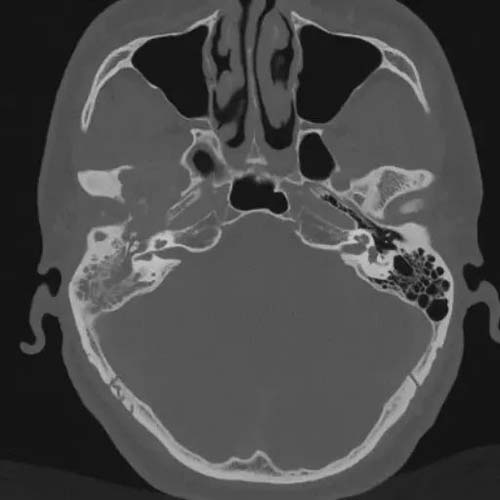

43岁的患者王先生(化名)因右耳反复闷堵听力下降3个月,辗转多家医院未得到明确诊断,遂来我院就诊。经杨会明主治医生、于淑东副主任检查,强化MRI可见王先生右侧颞骨岩部、颅底占位性病变突入颅内,肿物体积大、位置深。

考虑患者病变范围约4.5*2.7*4.2cm,病变较大,向上部分破坏颅底骨质进入颅内,向前影响颞颌关节,向内侧到达蝶窦外侧壁,向外到达上鼓室,如果不及时手术,任其自然发展,有可能会造成颅神经损伤、张口受限等并发症。于淑东副主任组织多学科会诊,鼻科何明强主任医师、神经外科许尚臣主任医师、口腔科郑培惠主任医师等共同研讨手术方式。